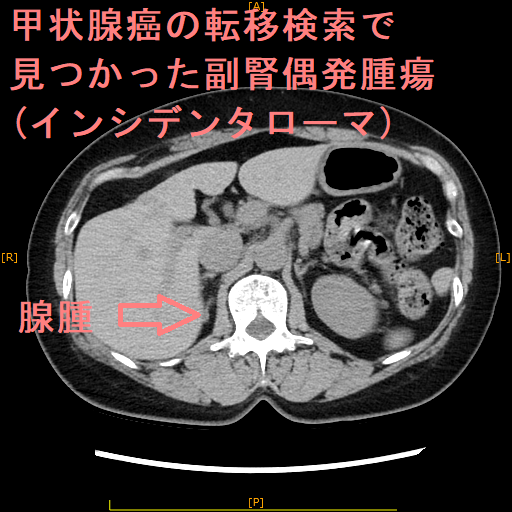

副腎は左右腎臓の上にあるのホルモン分泌臓器。副腎腫瘍はホルモンを作る機能性副腎腫瘍と作らない非ホルモン産生性腫瘍がある。腹部超音波検査やCTで偶然(1-5%、高齢者は10%)副腎腫瘍が発見される(副腎偶発腫瘍:インシデンタローマ)。約75%は副腎腺腫、約50%は非機能性副腎腺腫だが3cm以上なら副腎癌(副腎原発1%/転移性5%)の事がある。骨髄脂肪腫3%。機能性副腎腫瘍はクッシング症候群10%・褐色細胞腫10%・原発性アルドステロン症5%。単純CTでCT値が10HU未満の低吸収値になる副腎腫瘍は脂質を多く含む副腎腺腫。

腹部超音波検査やCTで偶然(1-5%、高齢者では10%)副腎腫瘍を発見される事があり、副腎偶発腫瘍(インシデンタローマ)と呼ばれます。

大阪大学の報告では、副腎偶発腫瘍(インシデンタローマ)の大半(77.0%)はCTで発見され、残りは腹部超音波検査(14.6%)、MRI(4.2%)、PET検査(4.2%)で同定。右側よりも左側に多く、腫瘍の平均直径は21±11mm。73.3%はホルモンを作らない非機能性副腎腫瘍。機能している腫瘍を有する患者は、機能していない腫瘍を有する患者よりも有意に若く、腫瘍の直径が大きかった。

一方、日本における全国的な多施設共同研究の結果、副腎偶発腫瘍(インシデンタローマ)の平均直径は3.0 ± 2.0 cm、50.8% が非機能性腺腫。非機能性腺腫と比較して、副腎皮質癌、褐色細胞腫、コルチゾール産生腺腫、骨髄脂肪腫、転移性副腎腫瘍、副腎嚢胞、および神経節神経腫では腫瘍直径が有意に大きい。

非機能性副腎皮質腺腫が3cm以上の場合、副腎癌(副腎原発1%/転移性5%)の事があります。